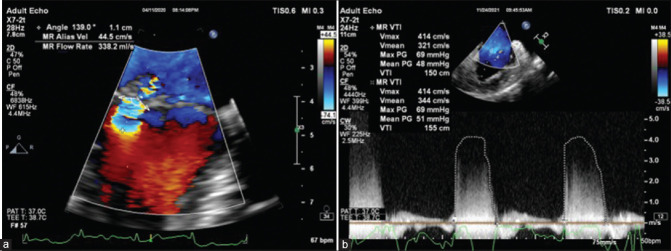

Background and aims: Intraoperative quantification of mitral regurgitation (MR) is sometimes necessary to quantify the severity of incidentally detected MR during cardiac surgeries. We aimed to compare and correlate the regurgitant volume (Rvol) and regurgitant fraction (RF) using 2D proximal isovelocity surface area (PISA) and 3D vena contracta area (VCA) with the 3D volumetric method and the integrated multiparametric approach.

Methods and materials: A prospective observational study was conducted on 37 patients undergoing mitral valve surgery for MR. Intraoperative quantification of the severity of MR was done using 2D PISA and 3D VCA methods and was compared with the 3D volumetric method. All three methods were compared with the integrated multiparametric method to obtain cutoff values for identifying severe MR.

Results: The correlation coefficients for Rvol with VCA and PISA with the 3D volumetric method were 0.688 and 0.58, respectively. VCA and PISA overestimated the Rvol (VCA = 77.93 ± 27.82 ml, PISA = 76.13 ± 19.25 ml) compared to the 3D volumetric method (66.12 ± 20.30 ml); the RF by the three methods was comparable. Using the receiver operating characteristic-area under curve (AUC) comparing Rvol by these methods with the integrated multiparametric method, the 3D volumetric method performed the best.